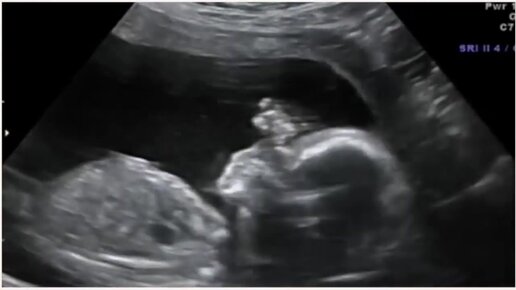

УЗИ на 20 неделе беременности